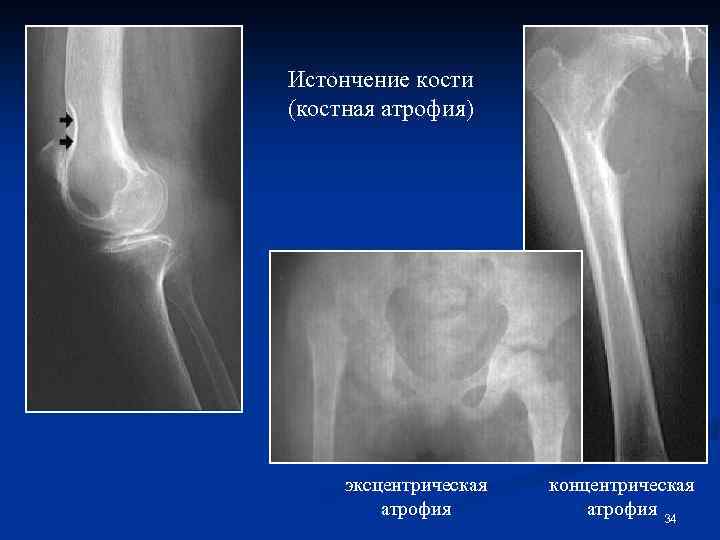

Истончение кости - истинная костная атрофия Врожденный процесс – гипоплазия Приобретенный процесс: Функциональная (от бездеятельности) Нейротрофическая Гормональная Атрофия от давления Старческая Формы костной атрофии: - эксцентрическая (рассасывание со стороны периоста и эндоста); - концентрическая (рассасывание со стороны периоста, наслоение со стороны эндоста). 33

Истончение кости (костная атрофия) эксцентрическая атрофия концентрическая атрофия 34